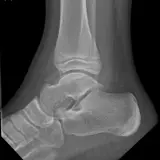

Over 2,100 interactive radiology cases, curated by radiologists for your level of training. Scroll, window, and view cases full screen — just like on PACS. Click linked findings in each writeup to jump straight to them on the image. Cases include sample reports, a focused discussion section, original illustrations, and videos.

Casos totalmente interativos com as ferramentas que você espera em um PACS — rolagem, ajuste de janela, zoom, movimentação, medidas, ROIs e modo de tela cheia.

Anotações detalhadas destacam os achados principais diretamente nos casos. Clique nos achados vinculados nas descrições dos casos para ir ao local exato no exame.